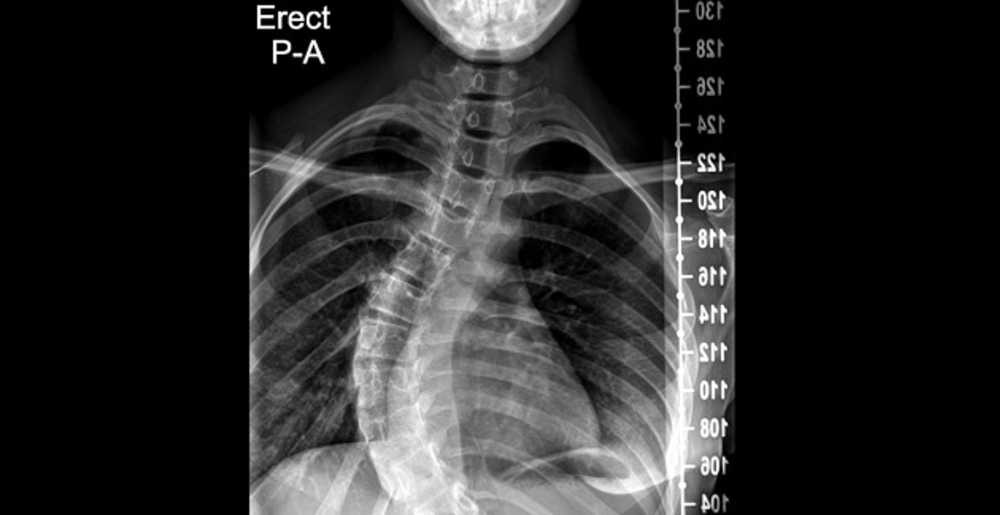

■背骨の病気・手術歴

側弯症や腰椎の手術(ボルト固定など)をしている場合、背骨が曲がっている、術後の炎症・癒着が激しい、ボルトなどの機械による狭窄によって背中のカテーテルがうまく入らなかったり、カテーテルを入れても麻酔が偏ってしまう(体の左右片方しか麻酔が効かない)リスクが上がってしまいます。